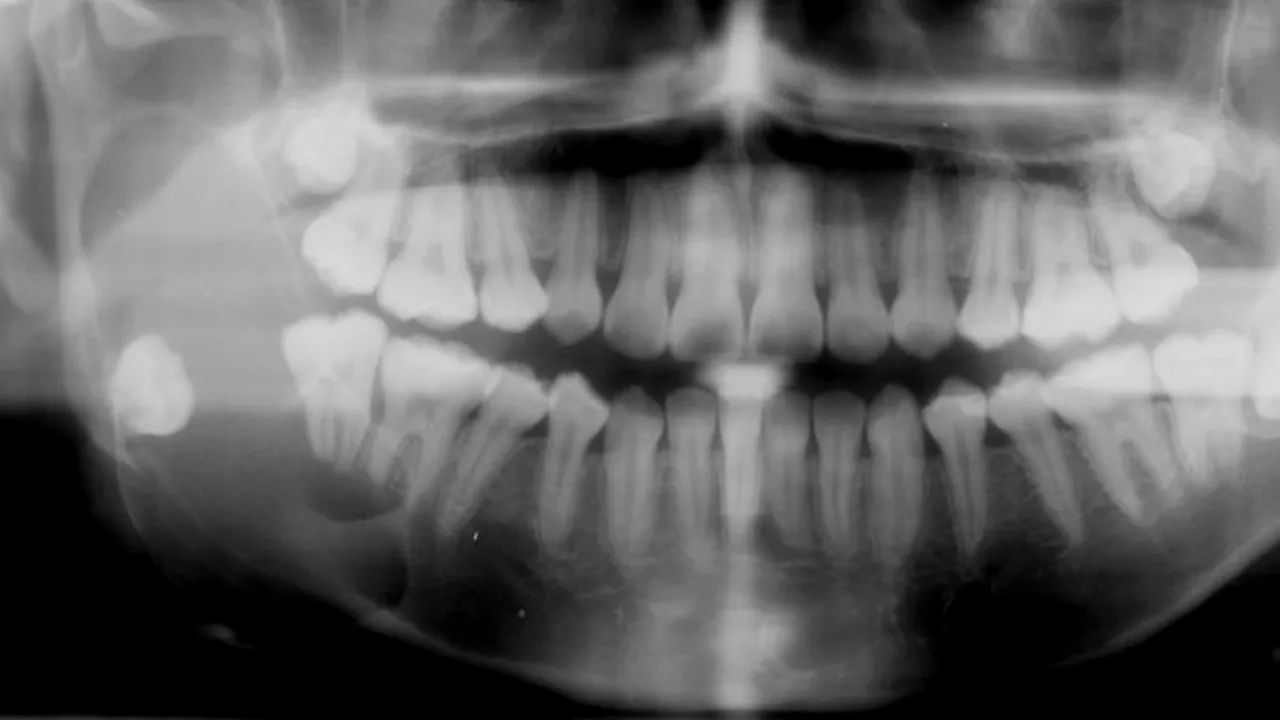

Medicul stomatolog Oana Florea explică cum a evoluat tehnologia și cât de sigure sunt radiografiile digitale în comparație cu alte surse de iradiere, notează CSID.

Conform spuselor specialistului, acestea sunt chiar mai sigure decât radiațiile cu care te confrunți atunci când zbori mult timp cu avionul.

„Radiografiile dentare joacă un rol foarte important în diagnosticul afecțiunilor dentare. Foarte mulți pacienți își fac griji în legătură cu expunerea la radiațiile Röntgen. Radiografiile digitale înlătură aceste temeri, deoarece necesită cu 90% mai puține radiații față de metoda convențională. În acest sens, 12-14 radiografii digitale necesită radiații cât 2 radiografii convenționale.

Dacă vă aflați într-un avion deasupra oceanului (10 ore la 10 km altitudine), vă expuneți la o cantitate de radiații egală cu cea necesară efectuării a 12 radiografii convenționale, sau a 120 de radiografii digitale, acestea fiind efectuate, în mod normal, și sub protecția șorțului de plumb”, declară medicul stomatolog Oana Florea.